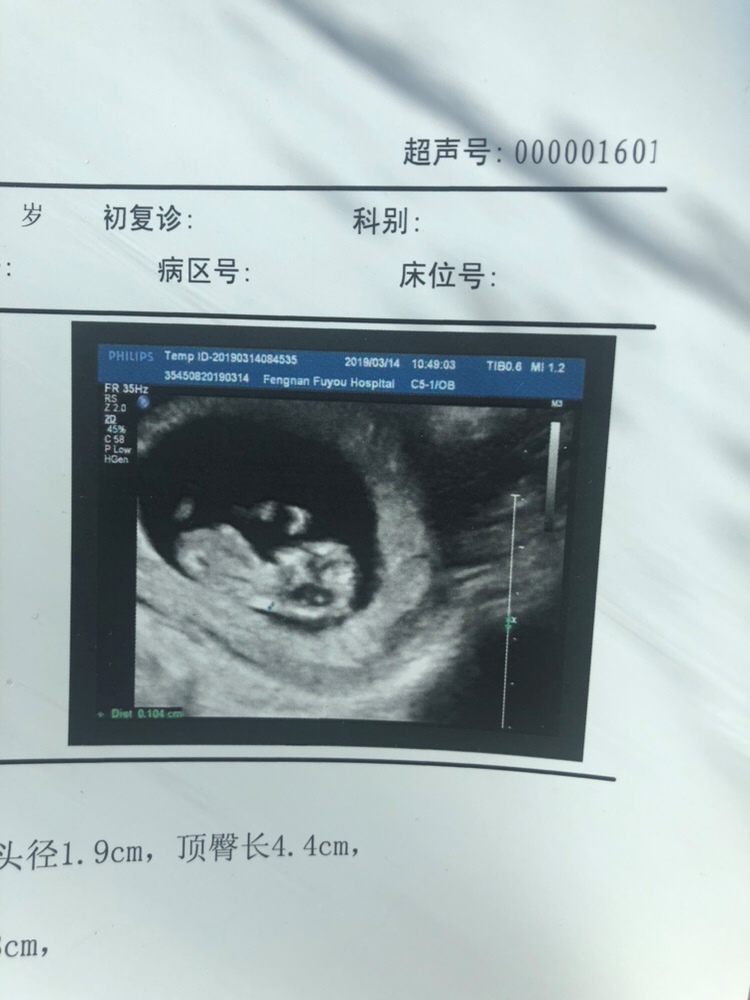

孕13周+0天